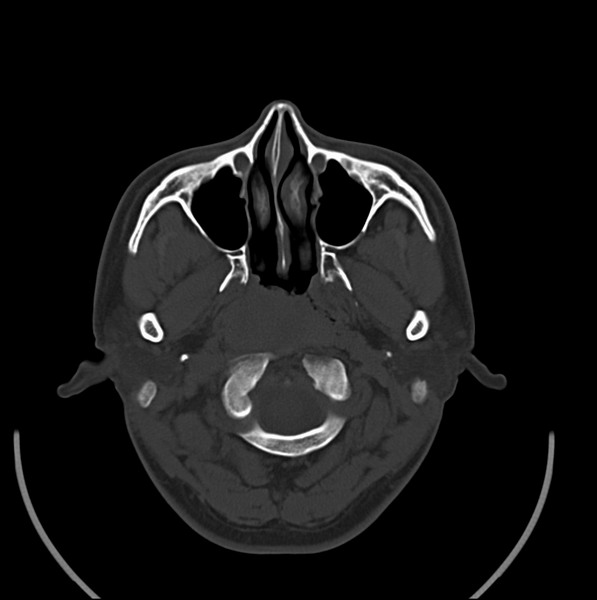

扫描示鼻咽腔不对称,中度狭窄,右侧咽隐窝消失,局部软组织肿块,鼻咽右侧壁增厚形成肿块,突入鼻咽腔,肿块平扫呈等密度,肿块向深部侵润,右侧翼内外肌受侵,右侧咽旁间隙变窄;向后生长,头长肌界线欠清,向后上生长侵犯同侧颈动脉鞘区。双侧海绵窦增宽,内见软组织影与鼻咽部肿块相连。考虑鼻咽癌。鼻咽癌主要是放射治疗,且效果较好;到当地有治疗设备较大医院治疗即可。

这个病例有点特殊,和常见的鼻咽癌不太一样,以向颅内侵犯为主,骨质破坏区小。鼻咽癌首先要考虑,有没有其他可能?本人不会看mr片,期待有人能讲解,期待病理。

鼻咽部新生物(纤维血管瘤?鼻咽癌?)侵犯右侧中颅窝底及右侧海绵窦;建议必要时活检定性。